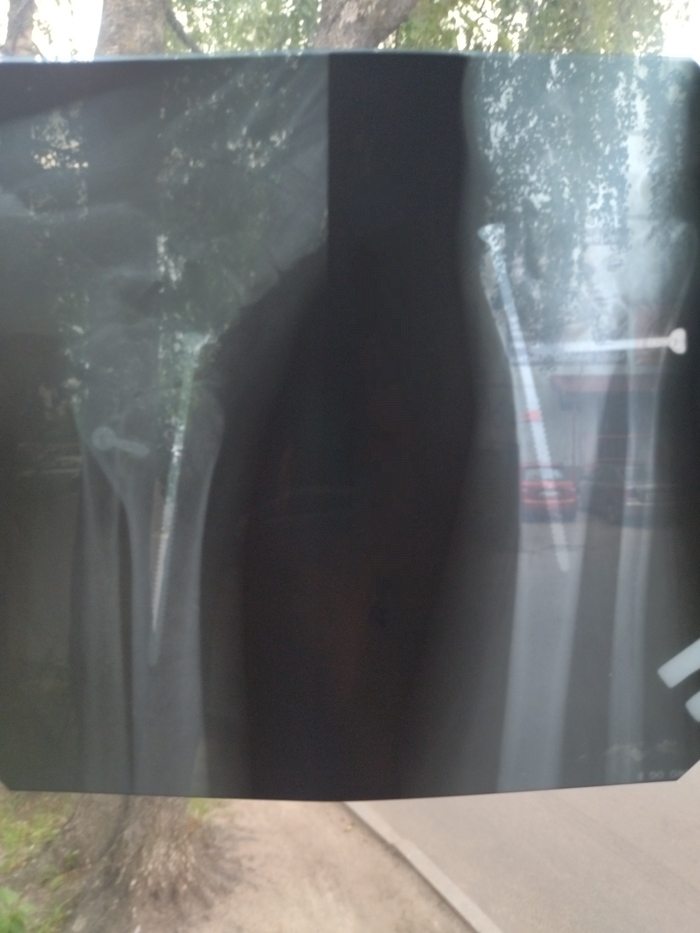

Пикабу помоги, мне нужно мнение 3 лица. 2 года назад моя мама сломала ногу. Была операция, вставляли винты. Сегодня сходили в диагностический центр, чтобы принять решение вынимать ли их и попали к другому врачу. Когда он увидел ренгент он присвистнул и сказал, что лично бы руки оторвал тому, кто оперировал. Сейчас она сильно хромает, нога постоянно болит,синяя поход по магазинам это уже ,как покорить эверест. Мы хотим понять какому врачу верить и к какому идти лечиться дальше. Вдруг, есть опытный травматолог, который бы просто указал путь дальше. Поднимите пожалуйста пост.

( Простите за качество фото рентгеновского снимка )

(Вид перелома спереди)

(Вид перелома с боку)

(Вид перелома сзади)

(Послеоперационный рентген)